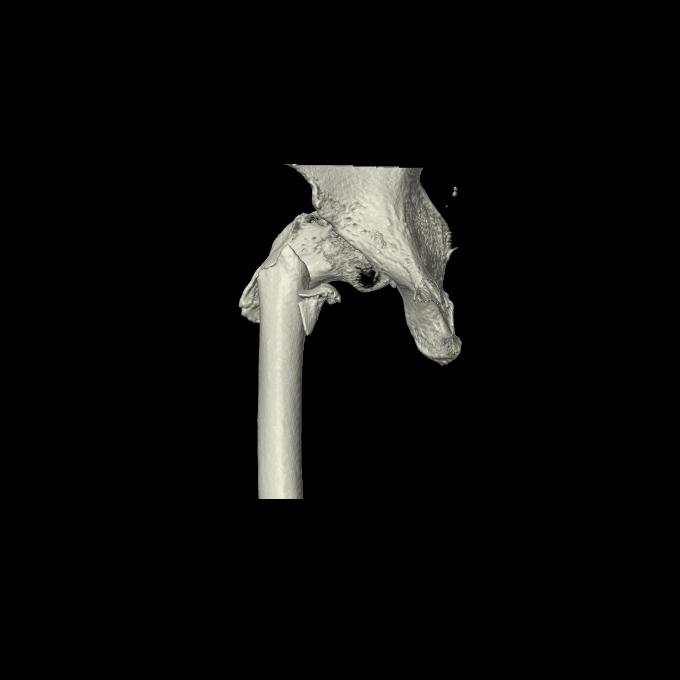

110286 2/17 股関節 2R 74歳女性 右人工骨頭